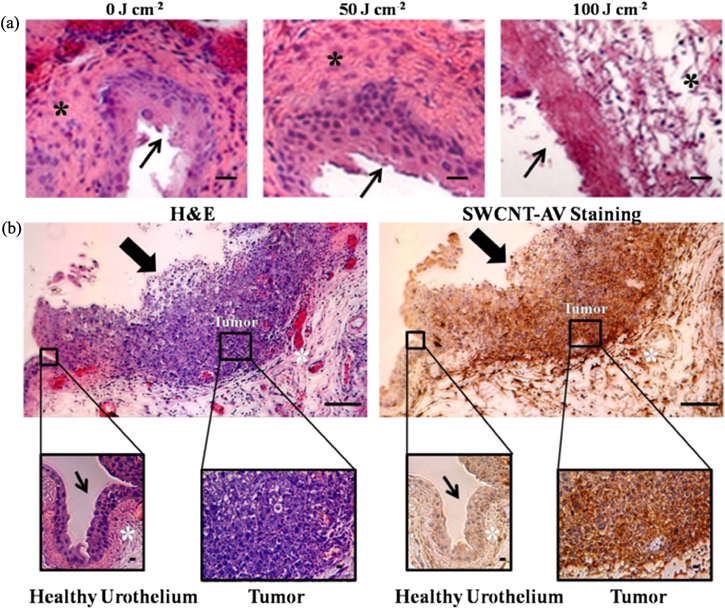

Tolerance studies on mice without tumours were conducted to determine the optimal energy for NIR radiation which will cause the tumour bound SWCNT AVs to heat without affecting the remainder of the urothelium. Figure 4(a) depicts H&E results from mouse bladders treated with 50 and 100 J cm−2 NIR light energy over 30 s as compared to a control bladder. Treatment with 100 J cm−2 resulted in apparent change in the urotheliumand muscle layer; however 50 J cm−2 led to no change.

Figure 4. In vivo NIR tolerance and tumour specific SWCNT-AV binding. (a) Mice (n = 3) were treated with 0 J cm−2, 50 J cm−2, and 100 J cm−2 NIR light energy over 30 s. Representative histology images show change to the bladder wall and deeper muscle layer in mice treated with 100 J cm−2. Mice treated with 50 J cm−2 NIR energy had no visible changes 24 h after irradiation. (b) Mouse with orthotopic bladder tumour was instilled with 100 μl of 20 mg l−1 SWCNT-AVs for 90 min followed by bladder collection 24 h later when NIR laser would be applied. Within the same bladder, dark brown, positive anti-AV staining for SWCNT-AVs is seen on the tumour while minimum staining is seen on the remainder of the urothelium. Thin arrow indicates healthy bladder wall, thick arrow indicates bladder wall with tumour, and * indicates muscle layer. Scale = 10 μm.

Standard image High-resolution image3.3. In vivo SWCNT-AV specific tumour cell binding

In order to benefit from a targeted therapy, non-specific binding needs to be minimised to prevent heating of healthy urothelial tissue. Anti-AV IHC confirmed that SWCNT-AVs were specifically bound to the tumour, and no binding was seen along the healthy bladder wall within the same animal (figure 4(b)).